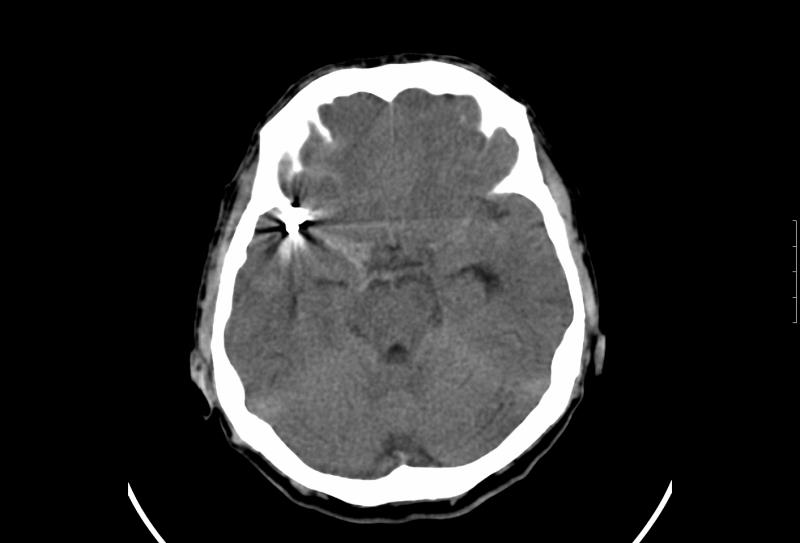

Άντρας ασθενής 55 ετών, νοσηλεύτηκε λόγω υπαραχνοειδούς αιμορραγίας και διαγνώσθηκε με ρήξη ανευρύσματος μέσης εγκεφαλικής αρτηρίας. Υποβλήθηκε σε ενδαγγειακή αντιμετώπιση με coils (εμβολισμός) και έλαβε εξιτήριο μετά την ολοκλήρωση της αγωγής του.

Πέντε μήνες αργότερα και παρά την ικανοποιητική αγγειογραφική εικόνα τόσο κατά τον εμβολισμό όσο και κατά τον επανέλεγχο στο μεσοδιάστημα, διαγνώσθηκε με νέα ρήξη του ίδιου ανευρύσματος, ενώ ο αγγειογραφικός έλεγχος κατέδειξε compaction των coil.

Στις προεγχειρητικές φωτογραφίες απεικονίζονται κατά σειρά ο αρχικός εμβολισμός, η εικόνα της επαναιμορραγίας σε αξονική τομογραφία και ο αγγειογραφικός έλεγχος μετά την επαναιμορραγία.